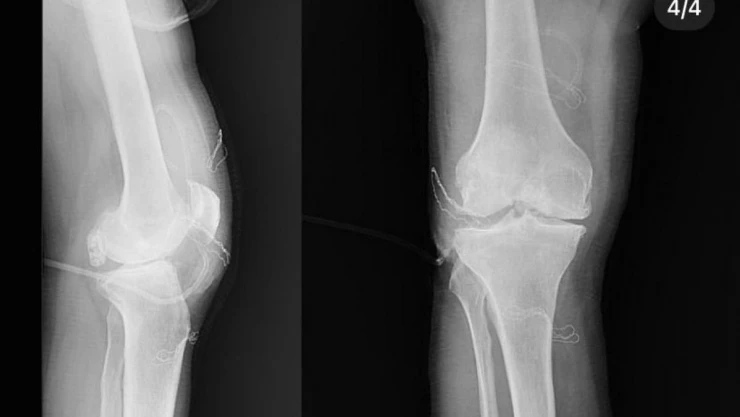

Diz ağrısı şikayeti ile geldiği Düzce Üniversitesi Tıp Fakültesi Hastanesi’nde ameliyata alınan hastanın dizlerinden toplam 41 adet multipl sinovial kondromatozisi çıkartıldı. Özellikle diz eklemi çevresinde görülmekle birlikte kalça, dirsek ve diğer eklemlerde de görülen, ufak parçalardan oluşan cisimler olarak tanımlanan eklem faresi, eklem çevresinde eklem sıvısı ya da sinoviyumda görülen kıkırdak ya da kemik parçalarıdır. Eklem farelerinin boyutları birkaç milimetreden birkaç santimetreye kadar çıkabiliyor.